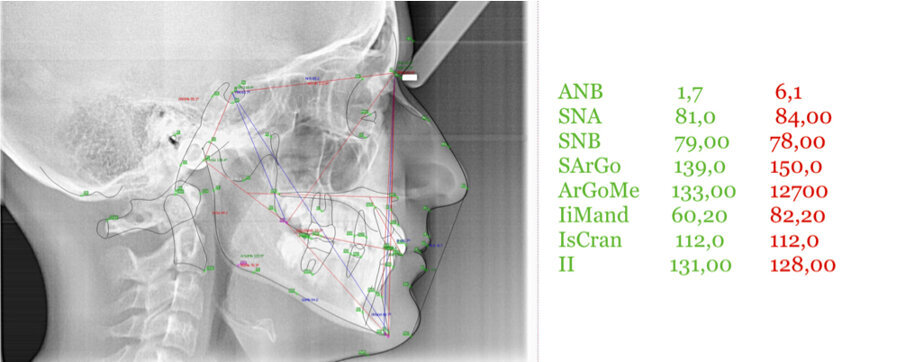

Caso 1 Paziente di anni 9,5, II Classe scheletrica, retrusione mandibolare, contrazione dell’arcata superiore, Overjet elevato (9,5 mm), compressione delle vertebre cervicali. La paziente riferisce di soffrire di cefalee continue. Dall’esame della panoramica e della teleradiografia evince una grande discrepanza tra il condilo dx e sx ed un evidente riduzione dello spazio intervertebrale in corrispondenza delle prime vertebre cervicali. La paziente è sottoposta a terapia elastodontica con AMCOP di seconda classe SC 3 con lo scopo di favorire l’espansione dell’arcata superiore e l’avanzamento mandibolare. A distanza di un anno evince un miglioramento dell’articolazione temporo-mandibolare di sx ed un aumento dello spazio intervertebrale legato a l’avanzamento mandibolare, è evidente inoltre il miglioramento dell’overbite ed overjet. A distanza di 2 anni si assiste ad un netto miglioramento dei condili grazie all’azione scheletrica dell’AMCOP ed a un netto vantaggio posturale con aumento dello spazio tra le vertebre cervicali. La malocclusione si può dire risolta anche se necessita una stabilizzazione del caso clinico attraverso lo stesso dispositivo (Figg. 2-14).

Il caso clinico dimostra come la malocclusione scheletrica avesse delle forti ripercussioni sulla postura e come risolvendo la malocclusione scheletrica si ha anche un ottimo equilibrio posturale come evince dalle teleradiografie.